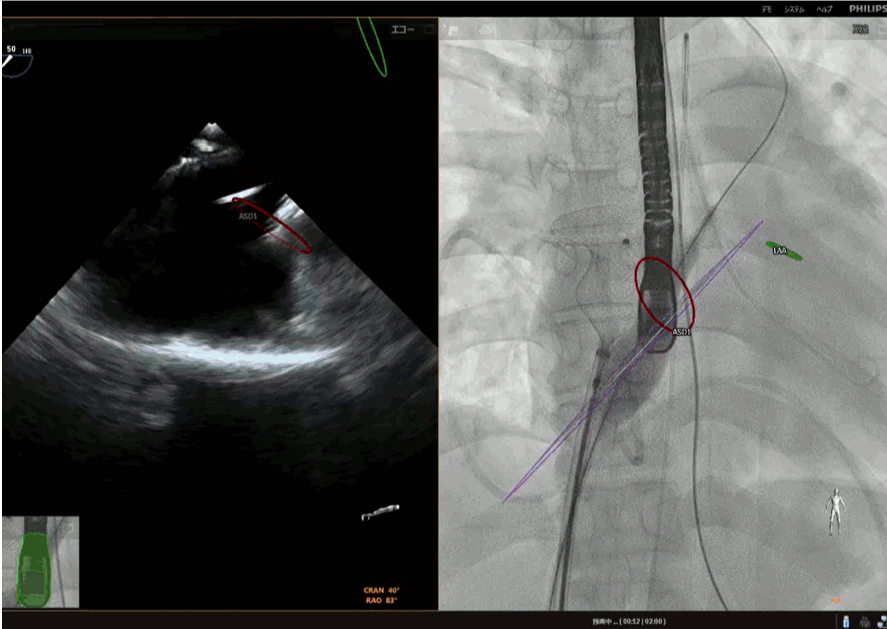

ASDカテーテル閉鎖術中の経食道心エコーとfusion imaging

ASDカテーテル閉鎖術中、ガイドワイヤーの操作のガイド方法は透視(X線装置)がメインとなります。一方、デバイスのサイズ決定~留置~留置後の確認は経食道心エコー(TEE) が主なガイド方法となります。その段階では術者も心エコーの画像をみながら手を動かすことが多くなります。TEE担当者は術者が常に見たいところが見えるように心がけています。

当院では通常のTEE画像に加え、ライブX線とライブエコーを融合するfusion imagingソフトのecho navigatorも使用して手技を進めています。TEEの走査面が透視画面上でどこかが一目瞭然となります。ハイブリッド手術室におけるこのようなfusion imagingの技術の進歩は近年めざましく、有用な手技補助手段として注目されています。

fUSION IMAGNINGの例

右図(透視画面)上の紫色の扇形は 経食道超音波TEE(左図)の走査断面を示します. TEE画面に表示されているのは透視画面上でどこか ということを把握することができます.